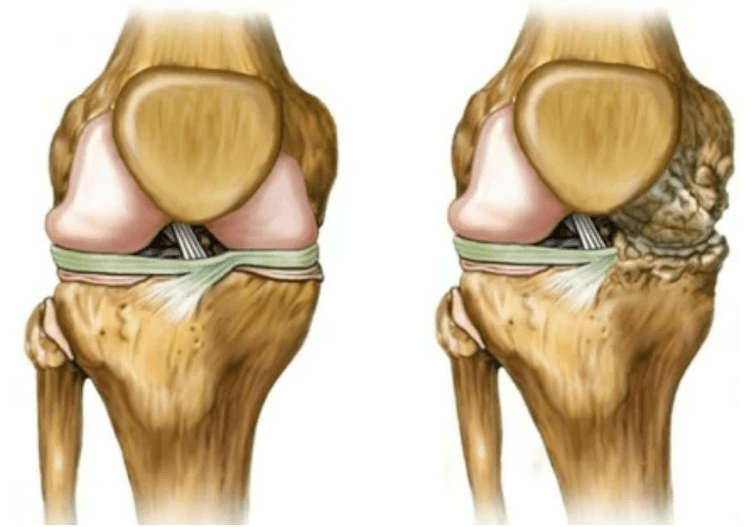

déformations des membres. Il apparaît d'une manière imprudente de la maladie, indique la destruction complète du tissu du cartilage et l'apparition d'ostéophytes. Dans cet état, la pression sur les articulations de la partie supérieure et inférieure augmente, à partir de laquelle la courbure peut affecter le membre entier.

Il est important de se rappeler que la déformation des os dans la jambe est souvent confondue avec le maïs. Le symptôme n'est pas très dangereux à première vue, mais entraîne de graves conséquences.

- L'articulation est complètement détruite;

- Le membre est immobilisé, tout mouvement devient extrêmement difficile;

- Forte déformation de l'articulation ou du membre entier.